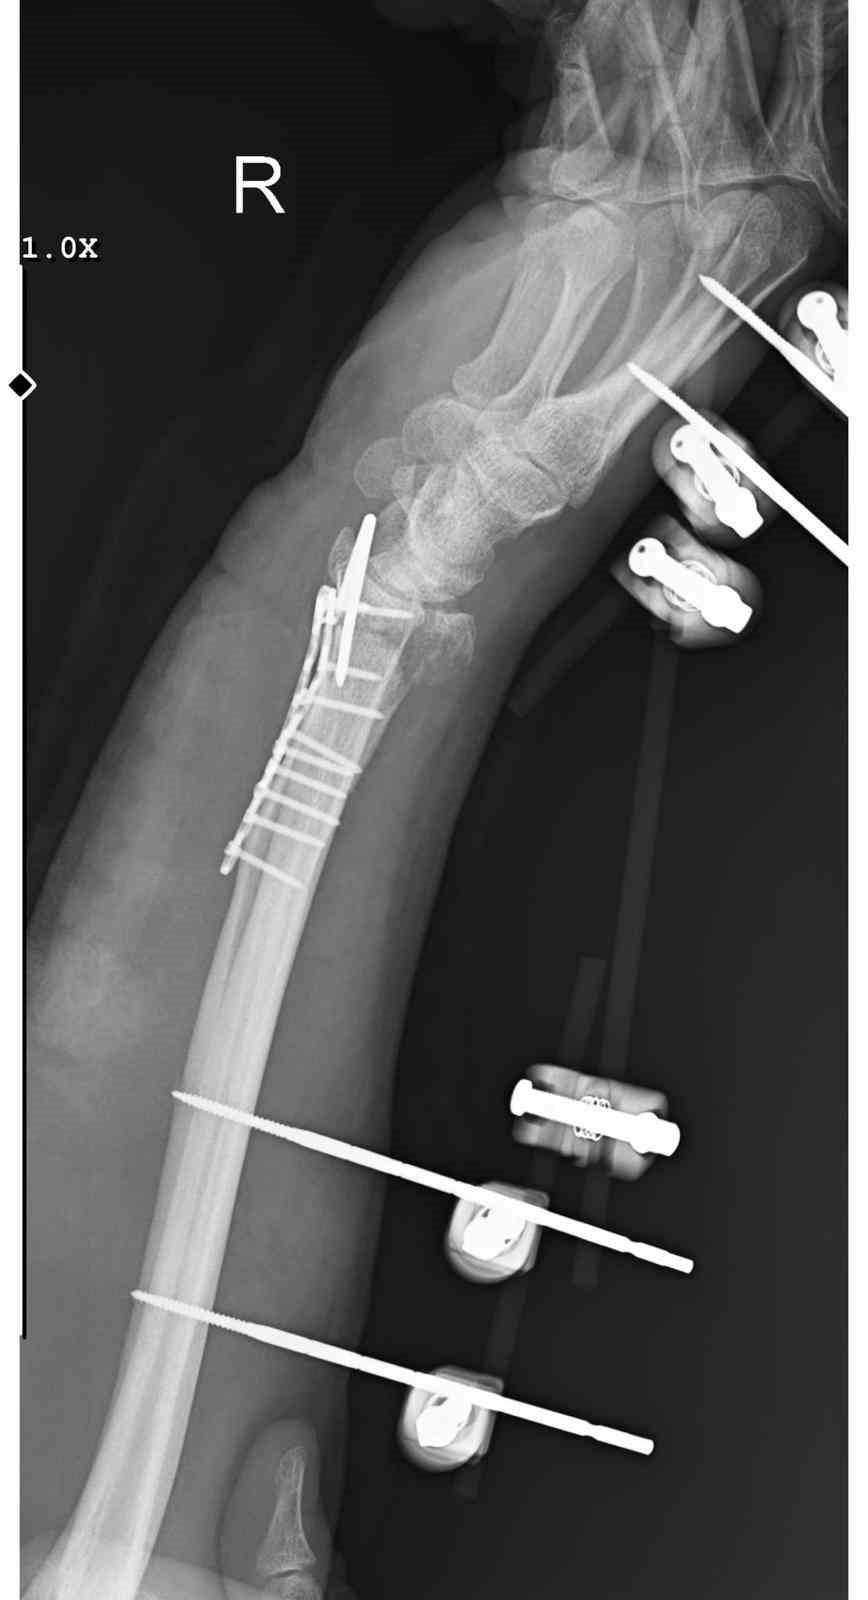

Ankara'nın Mamak ilçesinde, 29 Aralık günü meydana gelen olayda 35 yaşındaki Yasin Arslantaş, yaşadığı apartmanın önünde karşılaştığı sahipsiz köpeklerden kaçmaya çalışırken ayağının kayması sonucu düştü ve el bileği kırıldı. Olay sonrası ambulansla hastaneye kaldırılan Arslantaş'ın bilek kemiğine 11 adet platin yerleştirildi.

Arslantaş, olay anını şöyle anlattı: 'Sabah apartmandan çıkarken arkamdan 9 köpeğin geldiğini gördüm. Saldırganlardı. Kaçmaya çalışırken düştüm.' Yaralanma sonucu bileğinde 15 dikiş olduğunu, geçirdiği ameliyatın 3 saat sürdüğünü ve kolunda kalıcı his ile hareket kaybı olabileceğinin kendisine bildirildiğini söyledi.